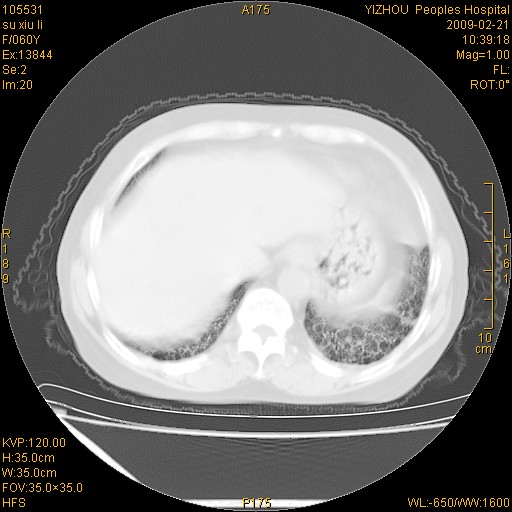

标题: CT18259:两肺间质纤维化?

女,60岁,反复咳嗽1月。

两肺支扩,以肺为著合并双肺较广范纤维化病变。建议除外结核等病变。

符合间质感染,部分纤维化表现

特发性间质纤维化

特发性间质纤维化伴支扩!